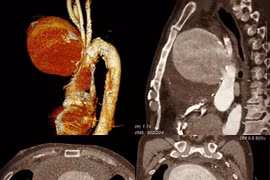

(khoahocdoisong.vn) - Bệnh viện quận Thủ Đức TPHCM vừa tiến hành can thiệp đặt stent-graft cho một bệnh nhân cao tuổi bị phình động mạch chủ bụng. Đây đã là ca thứ 4 thành công trong thời gian ngắn triển khai kỹ thuật cao cấp tại một bệnh viện tuyến quận.